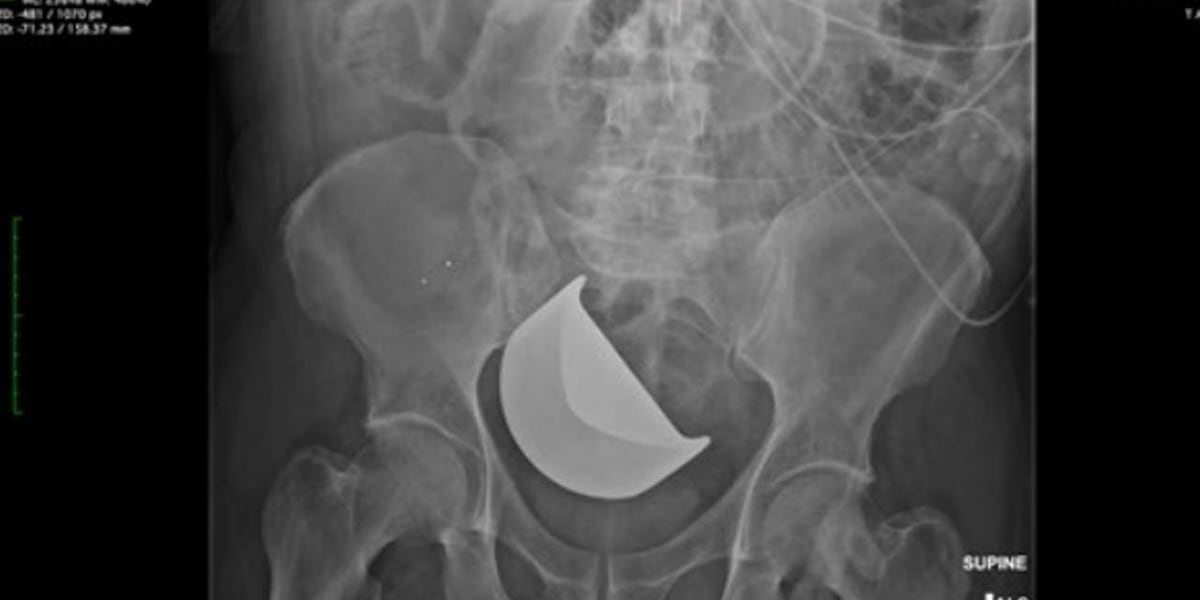

CHARLESTON, S.C. (WCSC) - South Carolina’s Insurance Reserve Fund has paid the estate of a Dorchester County man $1 million after doctors at the Medical University of South Carolina left a blade inside his abdomen during surgery, later resulting in his death.

Documents state that at some point in the surgery, a Thompson retracto